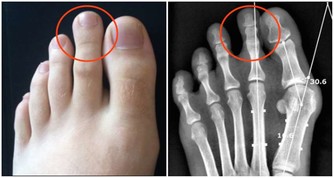

病人不宜多吃海產品,如海帶、海參、海魚、海蝦等,因其中含有尿酸,被人體吸收後,能在關節中形成尿酸鹽結晶,使關節症狀加重。